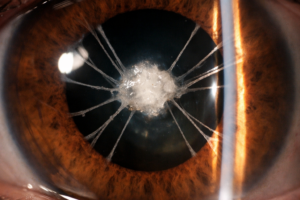

Persistance de membrane pupillaire étendue associée à une plaque capsulaire antérieure chez l’adulte La persistance de membrane pupillaire (ou Persistent Pupillary Membrane, PPM) est une anomalie congénitale fréquente, correspondant à…